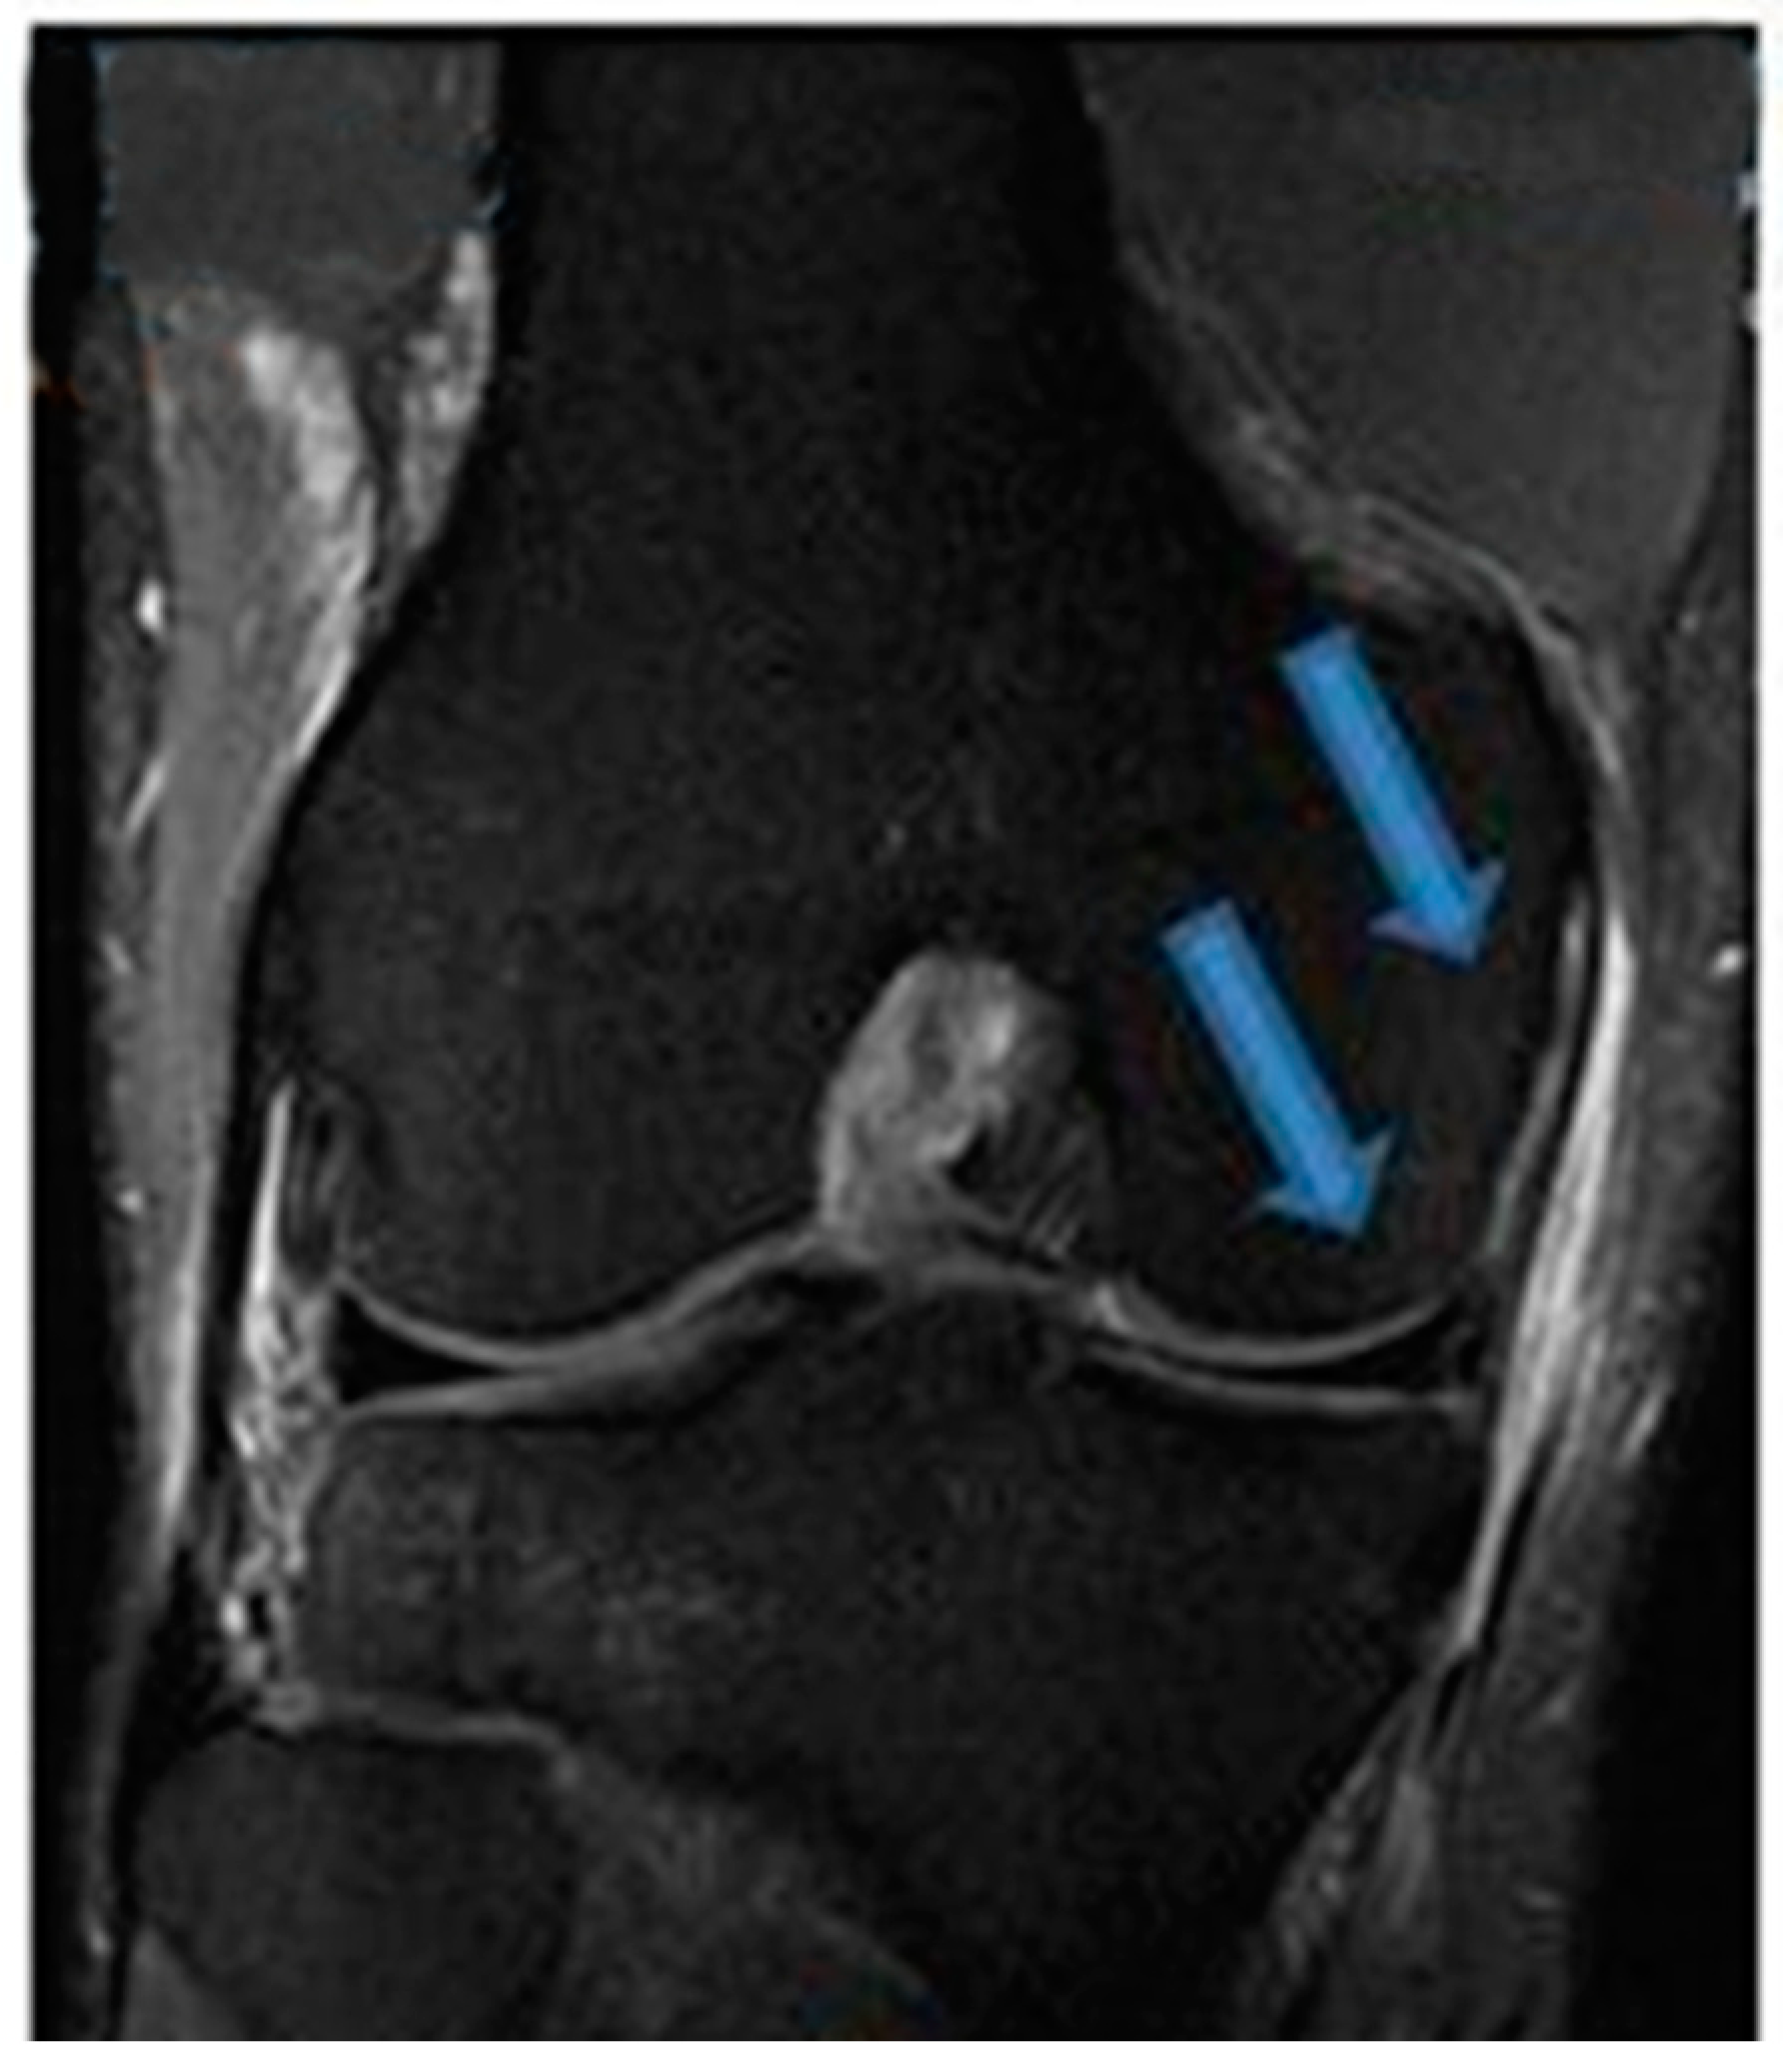

| 9 November 2020 | MRI scans demonstrating signs of partial ACL healing |

| 14 August 2021 | MRI scans demonstrating signs of complete ACL healing |

| 24 December 2021 | MRI scans confirming signs of complete ACL, MCL and medial meniscus healing |